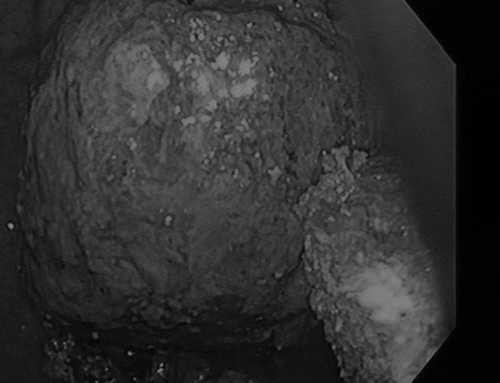

Các bác sĩ đã tiến hành nội soi dạ dày và bất ngờ phát hiện 4 khối bã thức ăn to như quả trứng trong dạ dày bệnh nhân, trong đó, 3 khối bã thức ăn có đường kính 4-6 cm và một khối to bất thường với đường kính trên 7 cm. Ngay sau đó, các bác sĩ đã tiến hành phẫu thuật gắp ra khối lượng lớn bã thức ăn trong dạ dày bệnh nhân.

Sau 4 ngày điều trị khối thức ăn của bà N. không thể tự cho ra ngoài được, các bác sĩ đã tiến hành mổ và lấy ra khối lượng hàng bát măng. Theo nhận định của các bác sĩ, nếu không can thiệp kịp thời khối bã thức ăn trên rất dễ gây bục ruột.